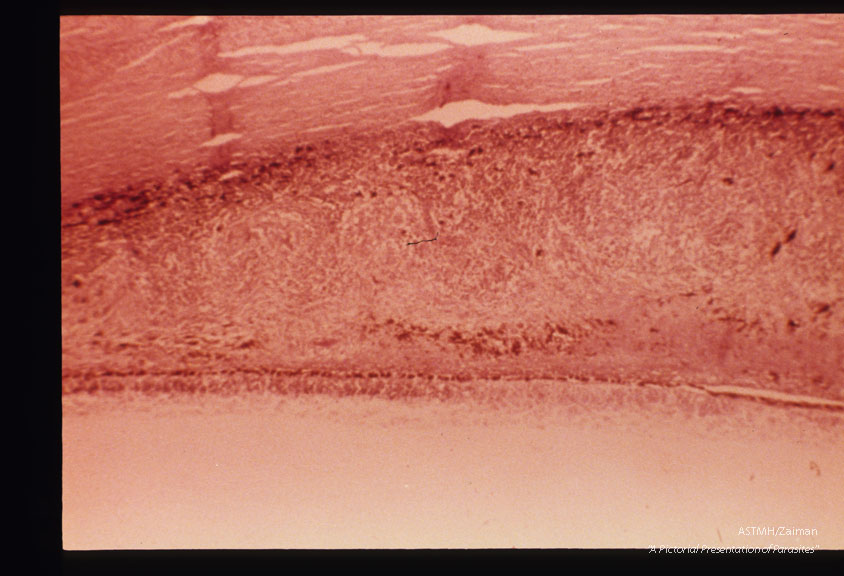

Toxoplasmic retinochoroiditis is associated with tachyzoites. Granulomatous reaction is present in choroid.

Toxoplasma gondii

Description: Toxoplasmic retinochoroiditis is associated with tachyzoites. Granulomatous reaction is present in choroid.